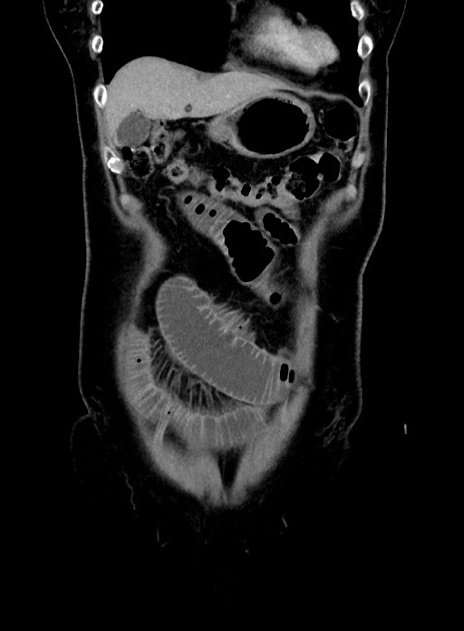

症例9(冠状断像)

症例

横断像

【症例】 60歳代女性

【主訴】むかつき、みぞおちの痛み

【現病歴】3日前よりむかつきがあり、食事がとれない。

【既往歴】糖尿病

【身体所見】発熱なし、心窩部圧痛軽度あるも、腹膜刺激症状なし。

【データ】WBC 7400、CRP 1.92